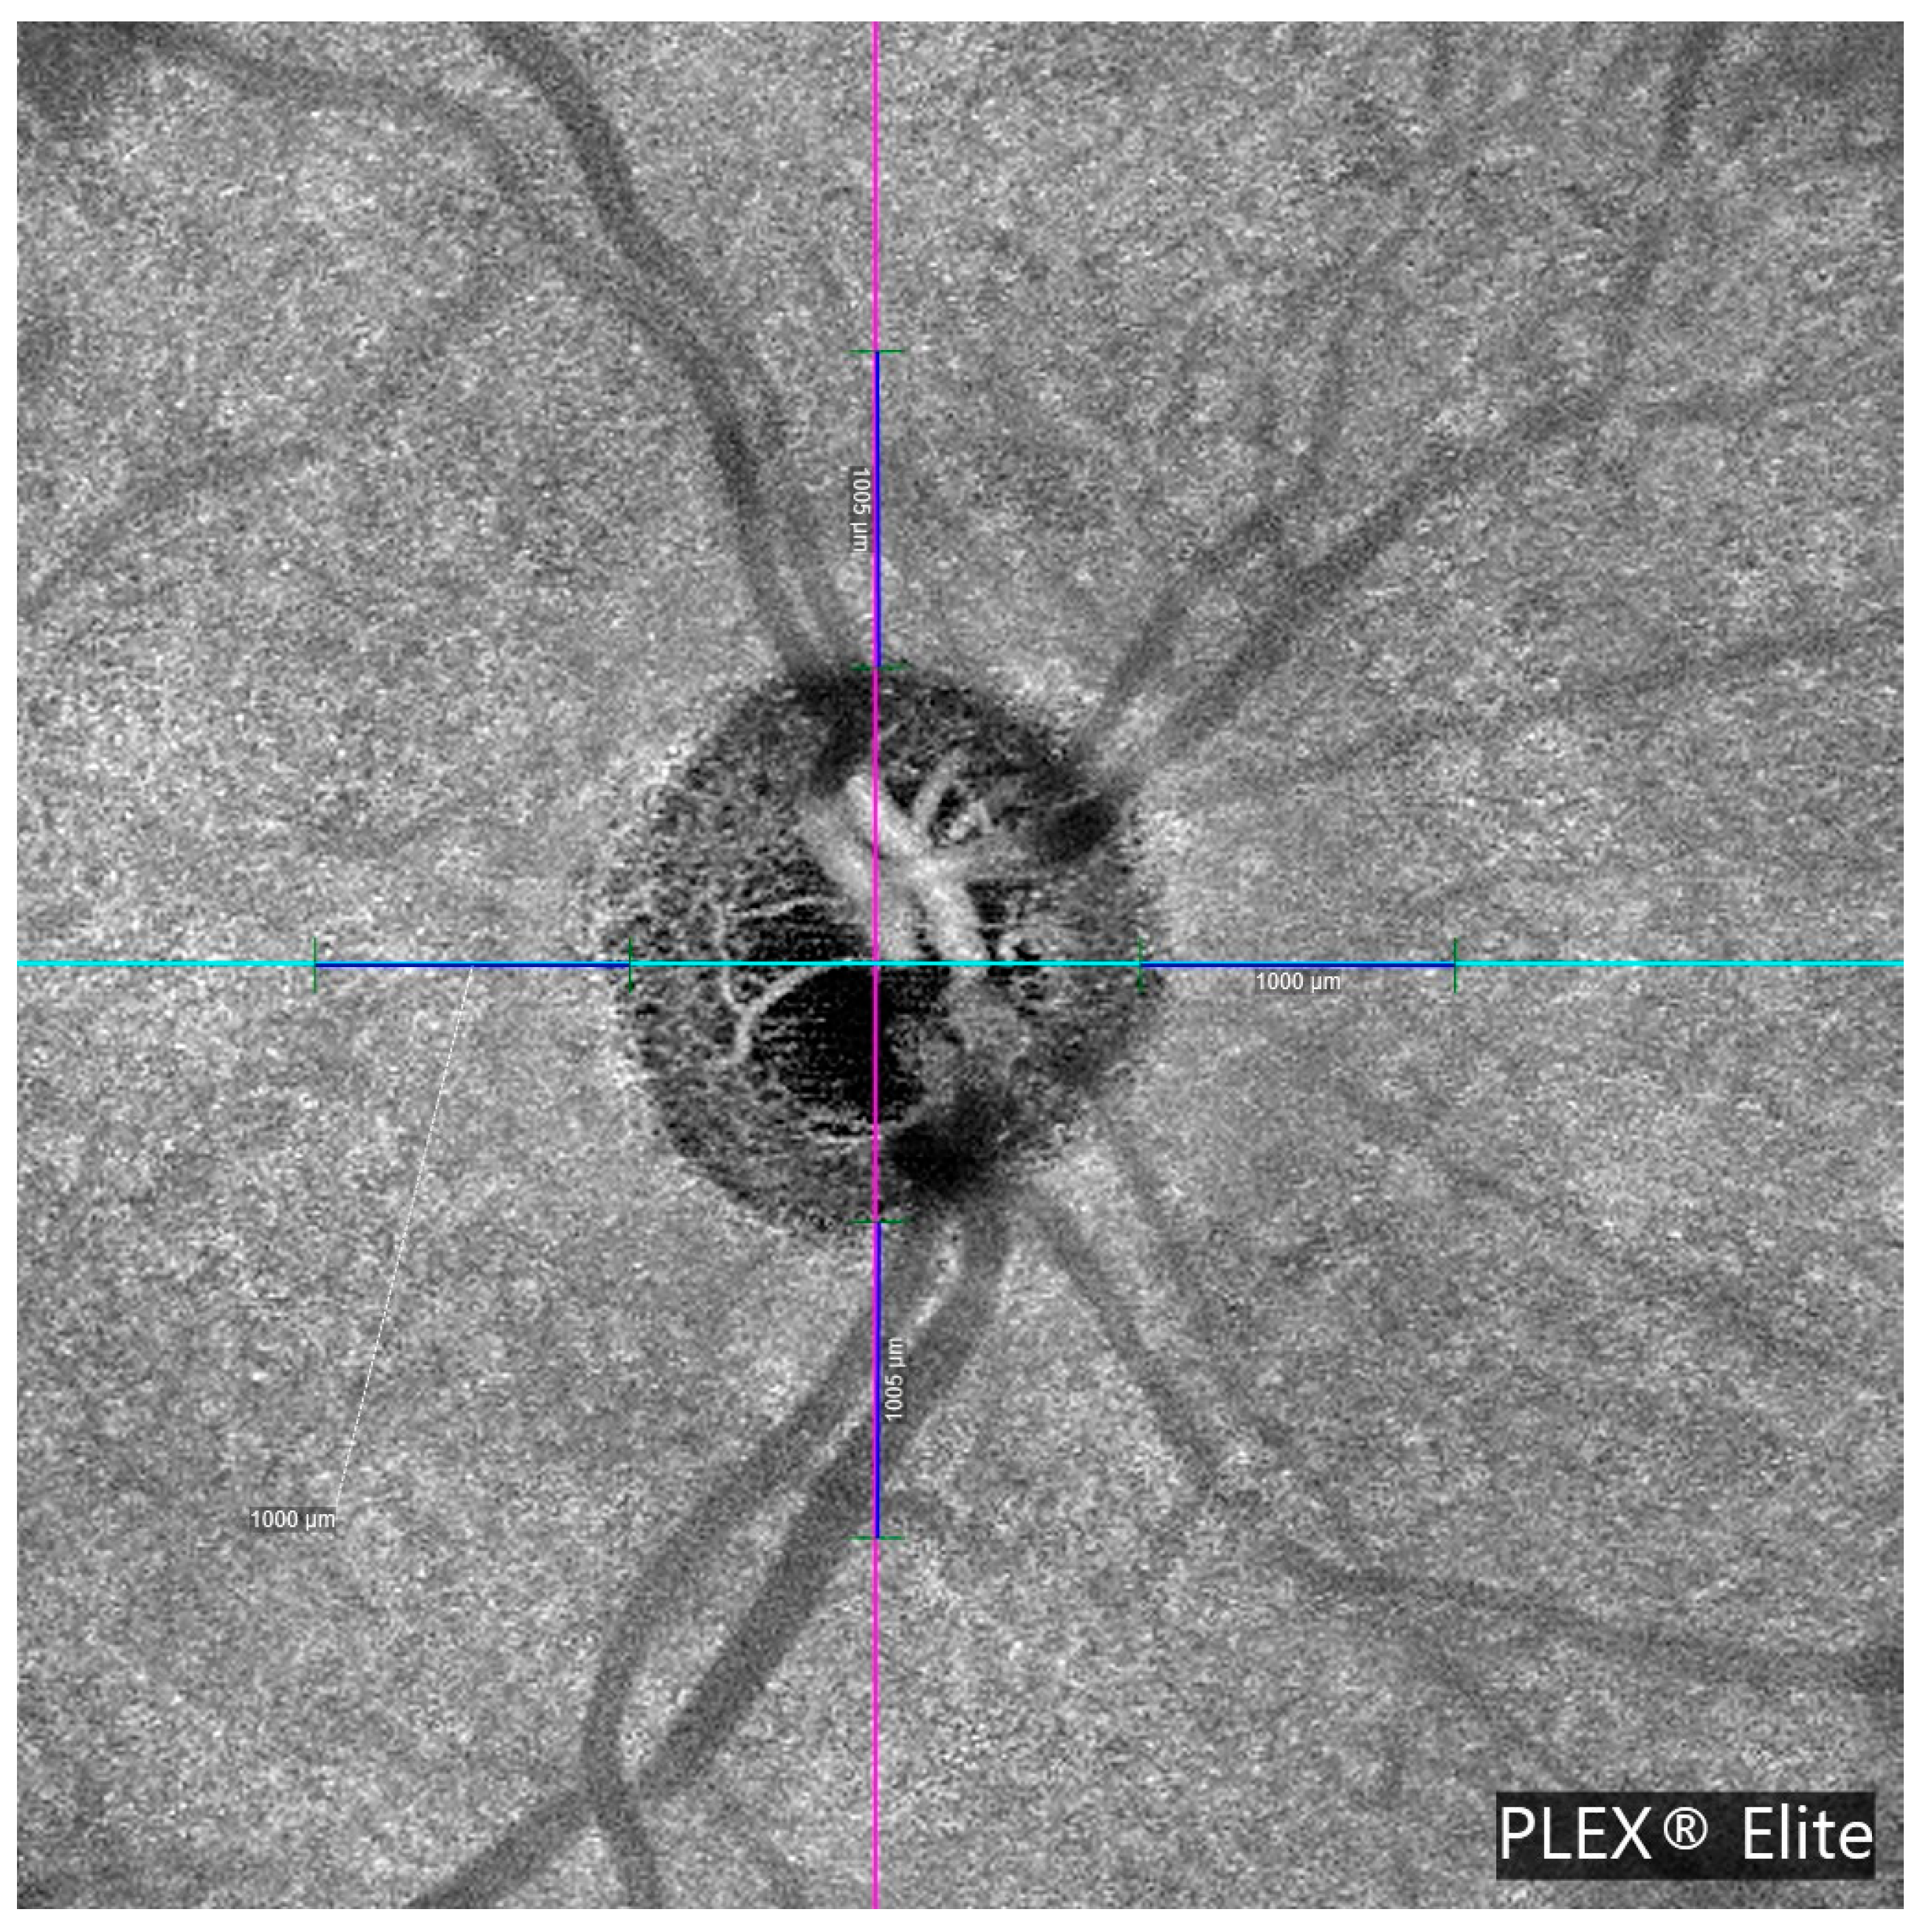

PCT is the thickness of the choroid (the vascular layer beneath the retina) measured in the peripapillary region. In this study, PCT was manually measured at a fixed distance of 1000 μm from the optic disc margin in the four peripapillary quadrants (temporal, nasal, superior, and inferior) using high-resolution en face OCTA images. Measurement points were selected based on two anatomical landmarks, specifically from the outer border of the retinal pigment epithelium (RPE) to the inner scleral boundary. This standardized approach was applied consistently across all subjects to ensure reproducibility and minimize measurement bias. The methodology is illustrated in Figure 1 and Figure 2.

β-zone parapapillary (β-PPA) was identified and quantified in the OCTA images. β-PPA was defined as the area between the optic disc margin (inner border of the peripapillary scleral ring) and the RPE atrophy line, characterized by visible sclera and prominent choroidal vessels. Manual delineation of the disc margin and β-PPA was performed on en face OCTA images using B-scan references. Figure 3 illustrates this process.

Figure 1. Optical coherence tomography angiography (OCTA) en face image of the optic nerve head (ONH) acquired using the PLEX® Elite 9000 system. The image displays the central optic disc with visible neuroretinal rim and radiating peripapillary vasculature. Colored crosshairs indicate horizontal and vertical measurement axes, each labeled with a 1000 µm scale reference. This image was used to manually delineate the optic disc margin and β-zone parapapillary atrophy (β-PPA) boundaries for structural analysis and to select the measurement points for choroidal thickness.